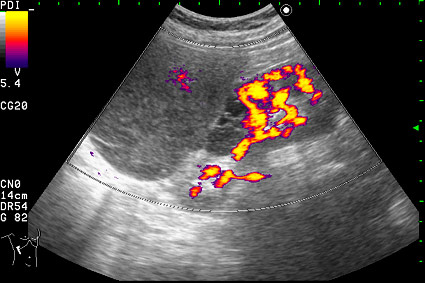

Образование в режиме энергетического доплера.

Почечно-клеточный рак правой почки, кистозная форма.

Но только по густому содержимому кистозного компонента. Стенка тонкая, кровоток не прокрашивается (единичный мелкий срез сосуда в центре образования больше похож на артефакт, а м.б. им и является).

Если бы в этом случае и содержимое было бы более "жидким", вероятность постановки правильного диагноза была бы минимальной.